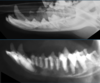

What is shown in these images?

nasal neoplasia: -left-sided -erosion of nasal septum -multifocal lysis -soft tissue nodule

49

nasal neoplasia: -soft tissue mass causing facial deformity -marked maxillary osteolysis -complete loss of turbinates; left more than right